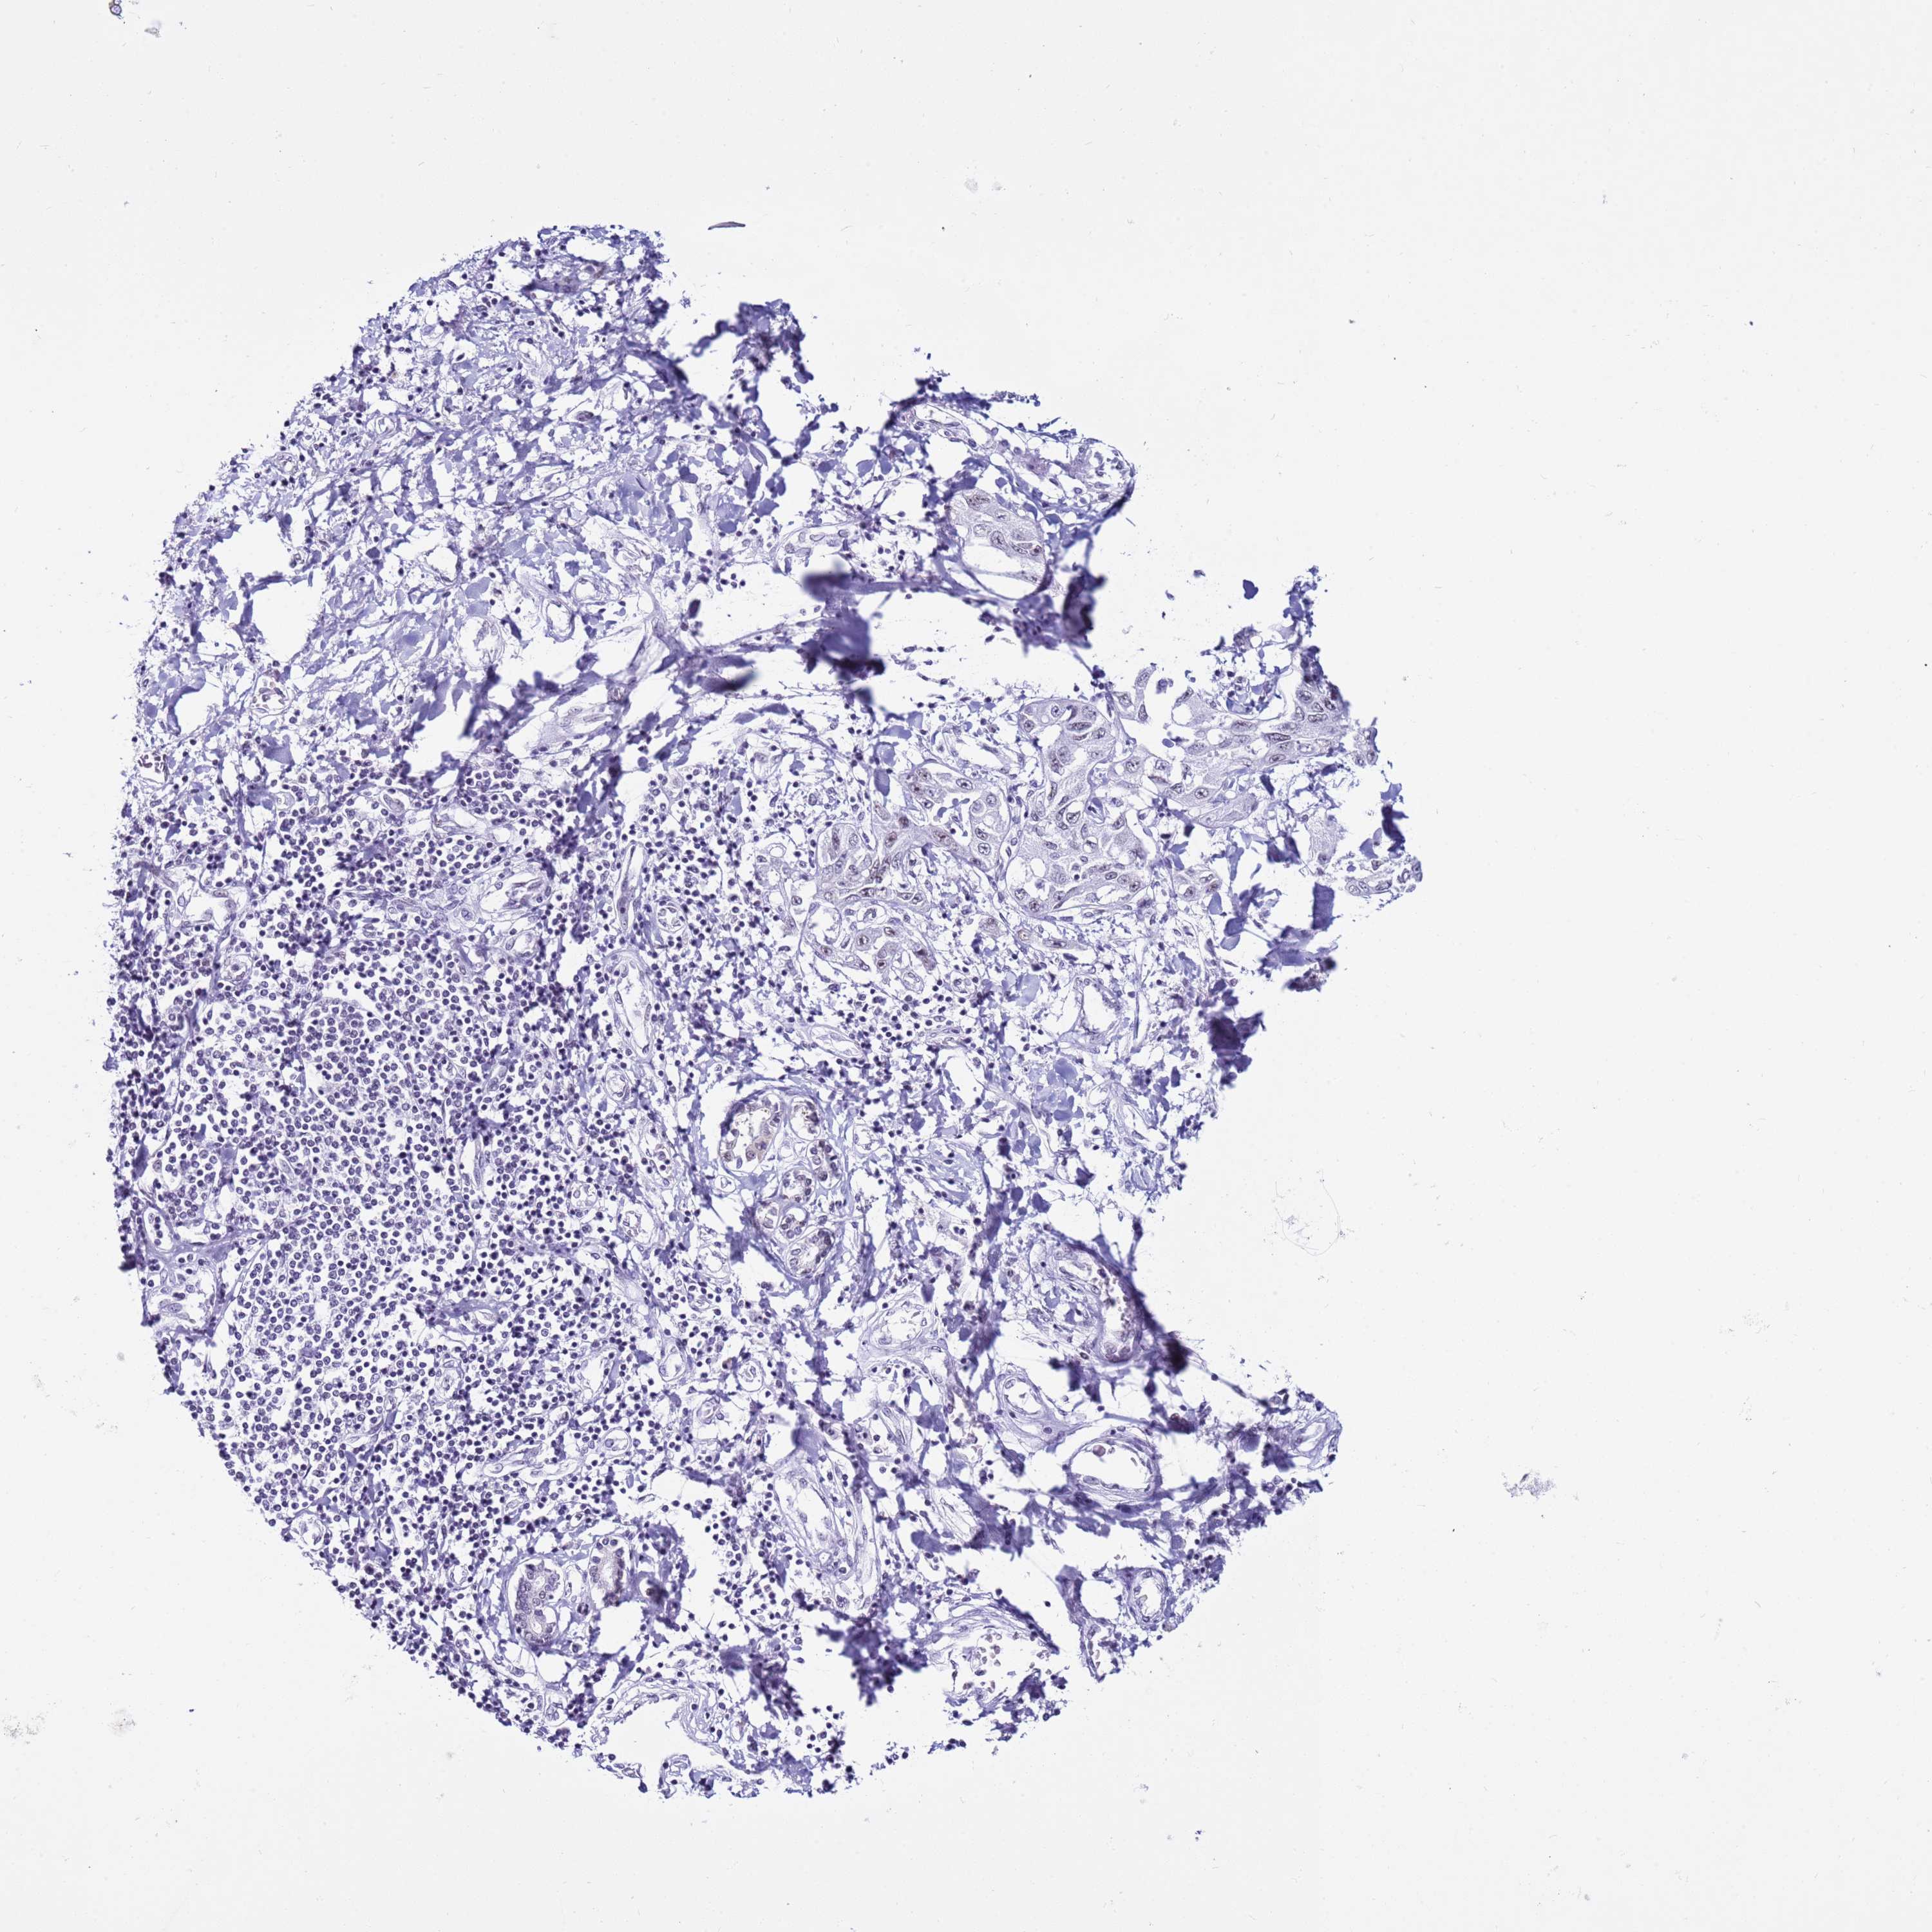

LIVER CANCER - Protein expressioni

A mouse-over function shows sample information and annotation data. Click on an image to view it in a full screen mode. Samples can be filtered based on level of antibody staining by selecting one or several of the following categories: high, medium, low and not detected. The assay and annotation is described here.

Note that samples used for immunohistochemistry by the Human Protein Atlas do not correspond to samples in the TCGA dataset.

Antibody stainingi

Antibody staining in the annotated cell types in the current human tissue is reported as not detected, low, medium, or high, based on conventional immunohistochemistry profiling in selected tissues. This score is based on the combination of the staining intensity and fraction of stained cells.

Each image is clickable and will lead to virtual microscopy that enables deeper exploration of all samples and also displays staining intensity scores, fraction scores and subcellular localization as well as patient and tissue information for each sample.

Antibody HPA047047

Staining

High

Medium

Low

Not detected

Intensity

Strong

Moderate

Weak

Negative

Quantity

>75%

75%-25%

<25%

None

Location

Nuclear

Cytoplasmic/membranous

Cytoplasmic/membranous,nuclear

Cholangiocarcinoma

Carcinoma, Hepatocellular, NOS